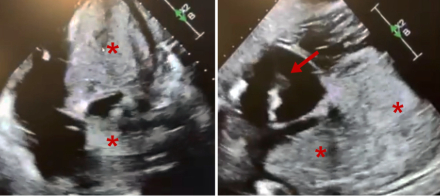

A 56-year-old male with a history of cardiac sarcoidosis with biventricular systolic heart failure (HF) and a bioprosthetic aortic valve presented with acute decompensated HF. Progressive cardiogenic shock and hemodynamic instability ensued, requiring urgent bedside placement of an intra-aortic balloon pump (IABP) which provided only marginal hemodynamic support. After extensive multidisciplinary discussion, emergent cannulation for veno-arterial ECMO (VA-ECMO) was performed at the bedside as a bridge-to-decision for advanced HF therapies. The IABP was left in place for LV venting. Within 72 hours, extensive bilateral pulmonary opacities had developed. It was later realized that true LV ejection (as evidenced by aortic pulsatility on the arterial line) was not present and had been masked by pseudo-pulsatility provided by IABP inflations and deflations. Compared to an echocardiogram done 7 days prior to VA-ECMO cannulation, the bioprosthetic leaflets were no longer opening, thrombosis of the AV had occurred, and thrombus formation along the ECMO venous drainage cannula was noted. Failure to achieve LV venting culminated in complete thrombosis of the entire LV and LA and the patient ultimately expired.